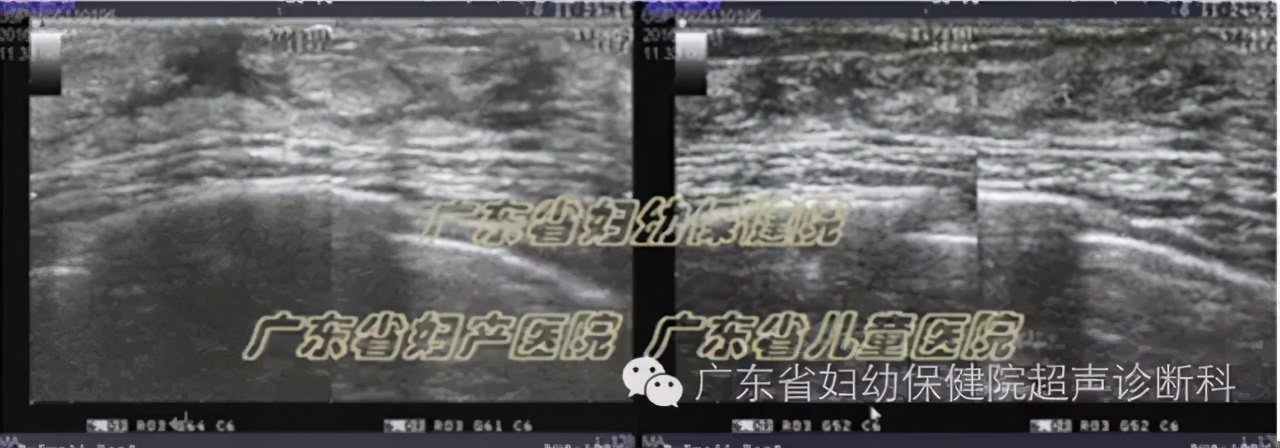

超声图像